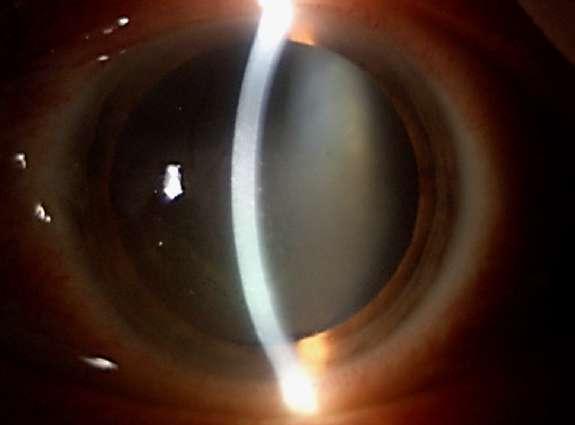

7.B. CATARATA LAMELAR

Imágenes aportadas por Dr. Álvaro Rodriguez

BAü La catarata lamelar también denominada zonular, es la más frecuente de las cataratas infantiles.

ü Se puede heredar en forma autosómica dominante.

ü Se presentan como opacidades bilaterales del núcleo y son el resultado de un daño al cristalino durante el desarrollo fetal siendo las capas más internas afectadas en mayor importancia mientras más precoz haya sido el daño.

ü Clínicamente se caracteriza por la presencia de opacidades en el cristalino que semejan protuberancias en forma de dedos proyectánddose a partir de un núcleo opacificado asociada con regiones de opacidad pulverulenta (Imagen A y B).

Messina O, González L, Cuevas S. Espectro clínico en una familia con catarata lamelar autosómica dominante. Rev Mex Oftalmol; Mayo-Junio 2005; 79(3): 163-165.